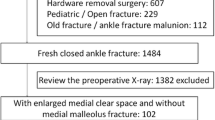

After exclusion of duplicates and non-English articles, there were 220 titles and abstracts reviewed, of which nine full-text studies were eligible. Of these studies, only three met inclusion and exclusion criteria, while the other six were excluded for not reporting any of the outcome measures of interest (Fig. 1).